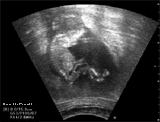

Die erste Blutuntersuchung (PAPP-A) wird zusammen mit einer zusätzlichen Ultraschalluntersuchung, bei der die sogenannte

Nackenfalte des Kindes ausgemessen wird, um die 10. Schwangerschaftswoche durchgeführt.